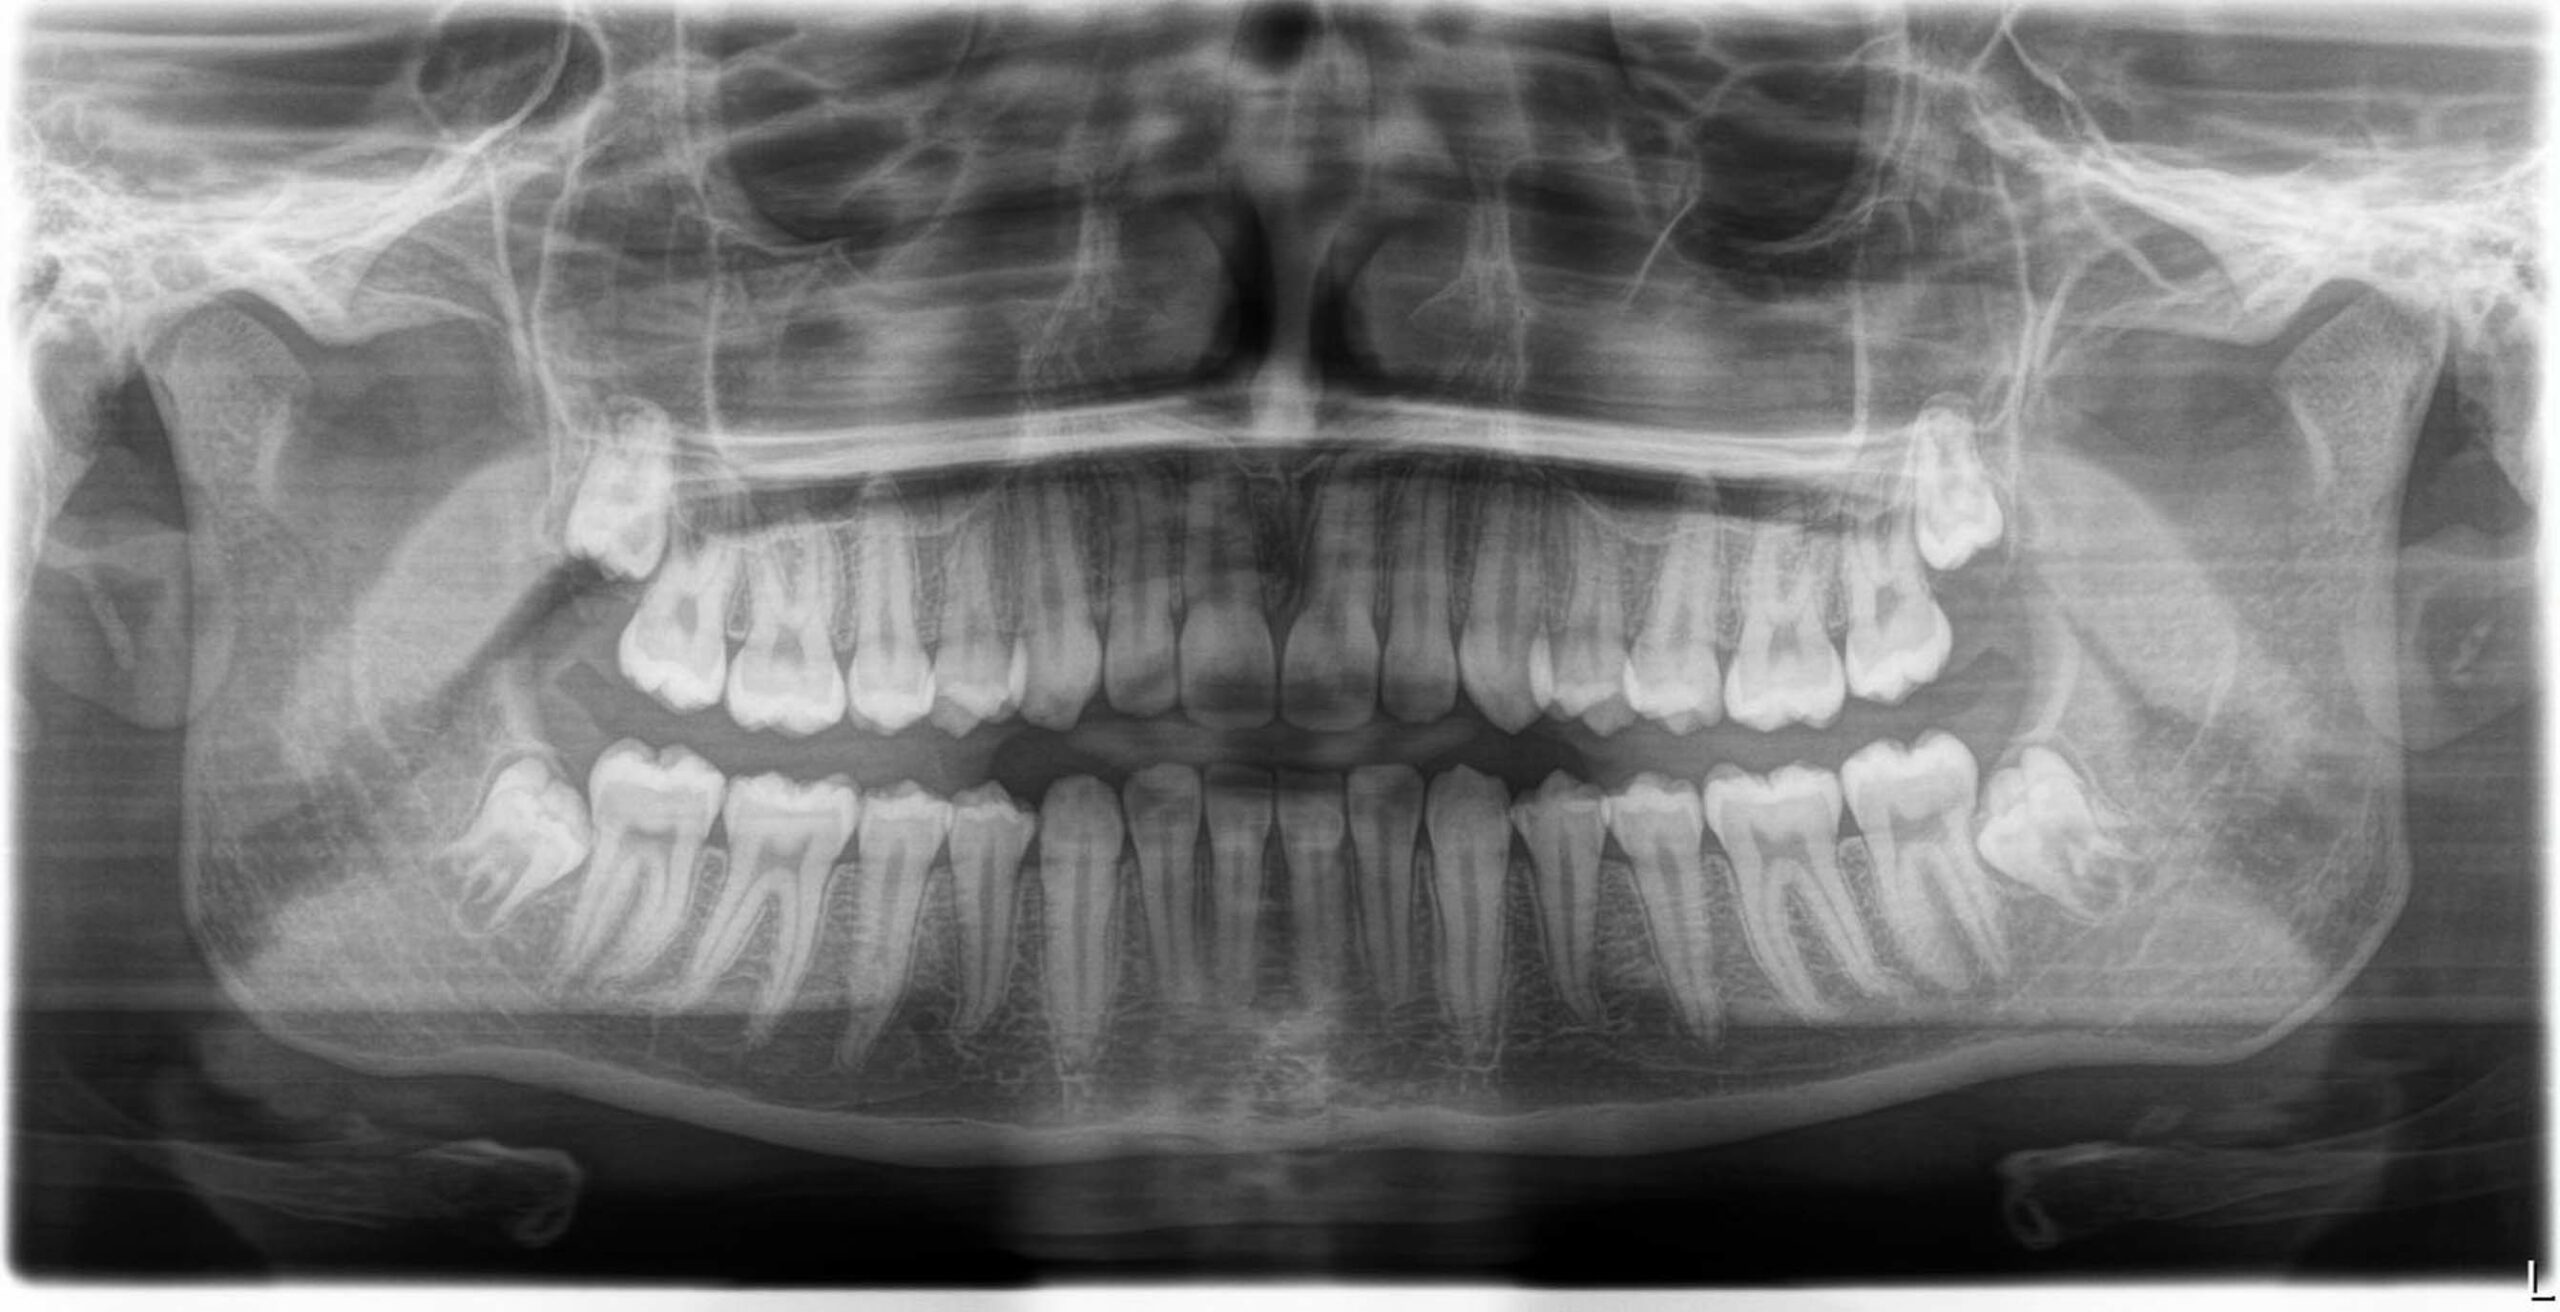

Bei über 80 % der Bevölkerung haben die Weisheitszähne zu wenig Platz im Kiefer und sollten idealerweise im jugendlichen Alter entfernt werden. Ein zu langes Zuwarten kann hier zu erheblichen Komplikationen führen.

Vorbereitend wird eine dreidimensionale Röntgenaufnahme ( DVT ) durchgeführt um das Risiko einer Nervverletzung für die Patient*innen zu minimieren. Diese Untersuchung kann seit 2019 auch in unserem Haus durchgeführt werden und wird von der Sozialversicherung finanziell unterstützt. Ebenfalls sollte vor dem Eingriff eine professionelle Zahnreinigung durchgeführt werden um das Infektionsrisiko zu reduzieren. Der Eingriff selbst dauert zwischen 30 und 60 Minuten.